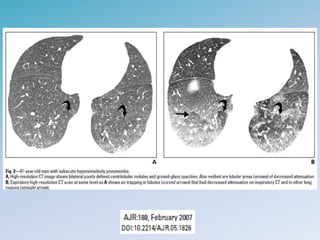

PNEUMONITE DE HIPERSENSIBILIDADE

• Radiologia

– Aguda: consolidações alveolares difusas ou em bases

– Subaguda: micronódulos mal definidos, opacidades em vidro

fosco e distribuição em mosaico

– Crônica: redução volumétrica, faveolamento, espessamento

septal, bronquiololectasias de tração

PNEUMONITE DE HIPERSENSIBILIDADE •Radiologia – Aguda: consolidações alveolares difusas ou em bases – Subaguda: micronódulos mal definidos, opacidades em vidro fosco e distribuição em mosaico – Crônica: redução volumétrica, faveolamento, espessamento septal, bronquiololectasias de tração • Bx Pulmonar + Histopatologico – Comprometimento bronquiolocentrico, com infiltrado linfocitario intersticial e granulomas mal formados • TTO: fim da exposicao + corticoterapia sistemica